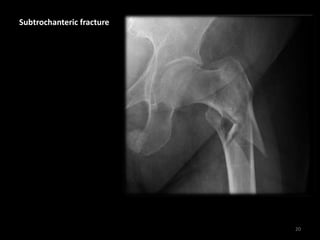

Subtrochanteric fracture

20

• This fracture passes

distal to the

trochanters

• The femoral neck

remains intact

21